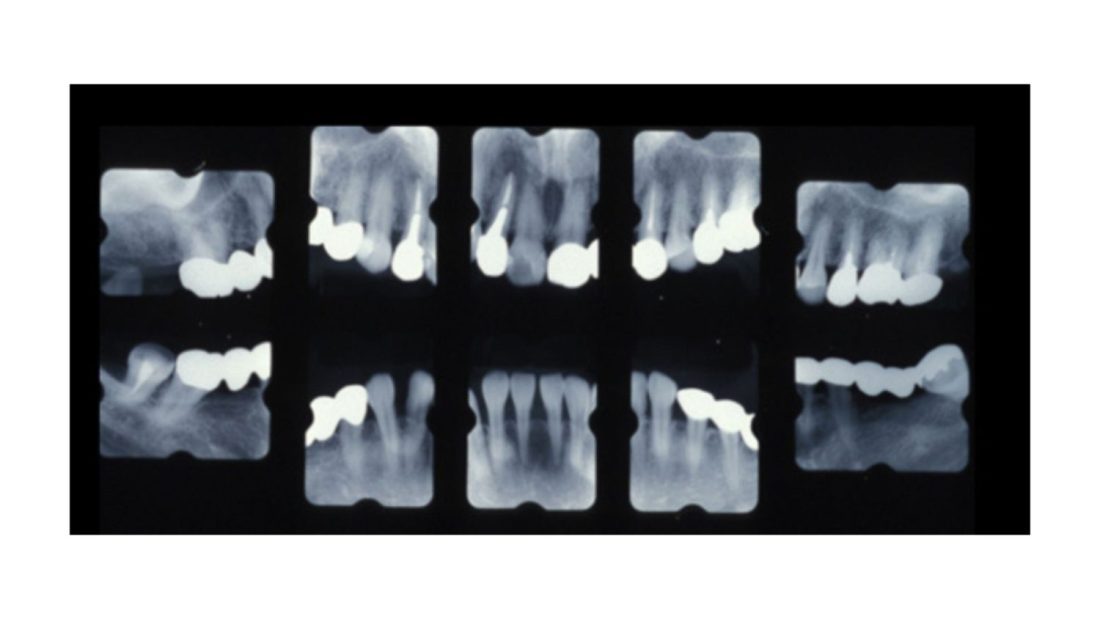

| 主訴 | 全顎治療希望、奥の歯茎から血が出る、綺麗で噛めるようになりたい |

| 治療内容 | 全顎的に歯周病、歯列不正が認められるため、歯周外科を含む歯周治療、矯正治療、インプラント治療、セラミックによる補綴治療後メインテナンスに移行 |

| 治療費 | 2,930,000円(税込)(インプラントすべて含む) |

| 治療期間 | 2年6ヶ月 |

| 治療回数 | 96回 |

| 想定されたリスク | 歯周病の再発、食いしばり(パラファンクション)によるセラミックの破折、歯の破折 |